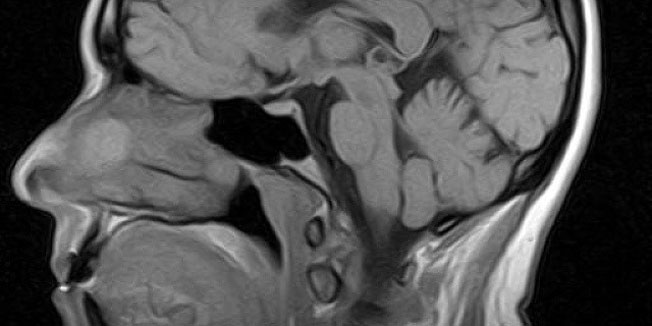

Loša vijest za one koji uzimaju lijekove za liječenje anksioznosti ili nesanice dolazi sa Sveučilišta u Bordeauxu. Naime, francuski znanstvenici su otkrili da dugotrajno uzimanje benzodiazepina, popularne skupine lijekova među kojima su diazepam (Valium) i alprazolam (Xanax), mogu više nego udvostručiti rizik za razvoj Alzheimerove bolesti.

Nekoliko manjih istraživanja je već ranije ukazalo na moguću povezanost između benzodiazepina i demencije, no ova velika studija je potvrdila i dodatno učvrstila ta saznanja.

Među odraslim osobama uključenim u istraživanje koje su uzimale te lijekove tijekom tri mjeseca ili duže u nekom periodu u prošlosti rizik za Alzheimerovu bolest je porasta...